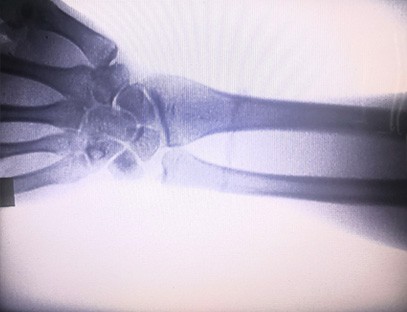

Una máquina de rayos X portátiles un instrumento portátil de baja dosis de radiación, muy seguro, que puede obtener imágenes de alta calidad al tiempo que reduce la exposición a la radiación. Compensa las deficiencias de los grandes equipos hospitalarios y se puede mover y transportar en cualquier momento. Especialmente adecuado para unidades e individuos con presupuesto insuficiente y bajos requisitos de imágenes. Nuestra máquina de rayos X de nueva generación está equipada con una pantalla grande de alta definición de 10 pulgadas, que tiene un rango de ángulo de visión más amplio y puede ver completamente a través de toda la palma, incluidas fracturas, dislocaciones, artritis y tumores óseos. Se puede conectar a una impresora de películas para imprimir películas ortopédicas y también se puede utilizar para producción y pruebas industriales. No necesita un cuarto oscuro, perspectiva directa, observación en tiempo real. Esta máquina tiene un sistema de imágenes de alta resolución que puede capturar imágenes de cualquier estructura ósea con mucha claridad. Proporcionar los mejores equipos y soluciones de prueba de rayos X para fabricantes de productos médicos, de mascotas, industriales, electrónicos, departamentos de inspección y mantenimiento y laboratorios de investigación.

Especialización:Diseñado para las necesidades de las clínicas ortopédicas, especialmente adecuado paraImágenes de rayos Xde extremidades como manos, muñecas, codos, hombros, rodillas, tobillos, etc.

Imágenes claras:Se utiliza tecnología avanzada de imágenes digitales para proporcionar imágenes de rayos X de alta calidad, lo que ayuda a los médicos a diagnosticar la afección con precisión.